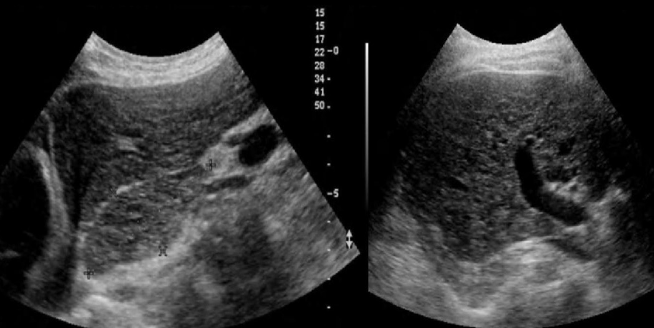

Identify this image.

Chronic hepatitis